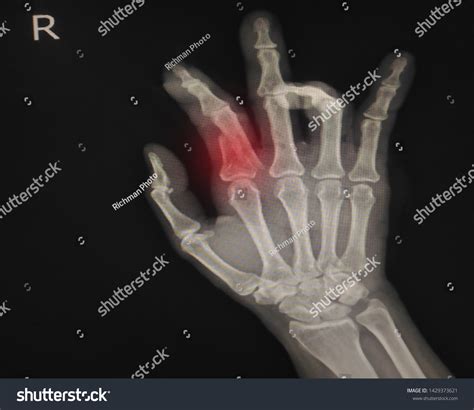

• X-rays: X-rays are the primary imaging tool used to confirm the presence and type of fracture. They provide detailed images of the bones and can help determine the severity of the injury.

Boxer's Fracture A specific type of metacarpal fracture, often involving the fourth or fifth metacarpal. Punching a hard object with a closed fist.

Bennett's Fracture A fracture of the base of the first metacarpal bone, often involving the thumb. Falls or direct trauma to the thumb.